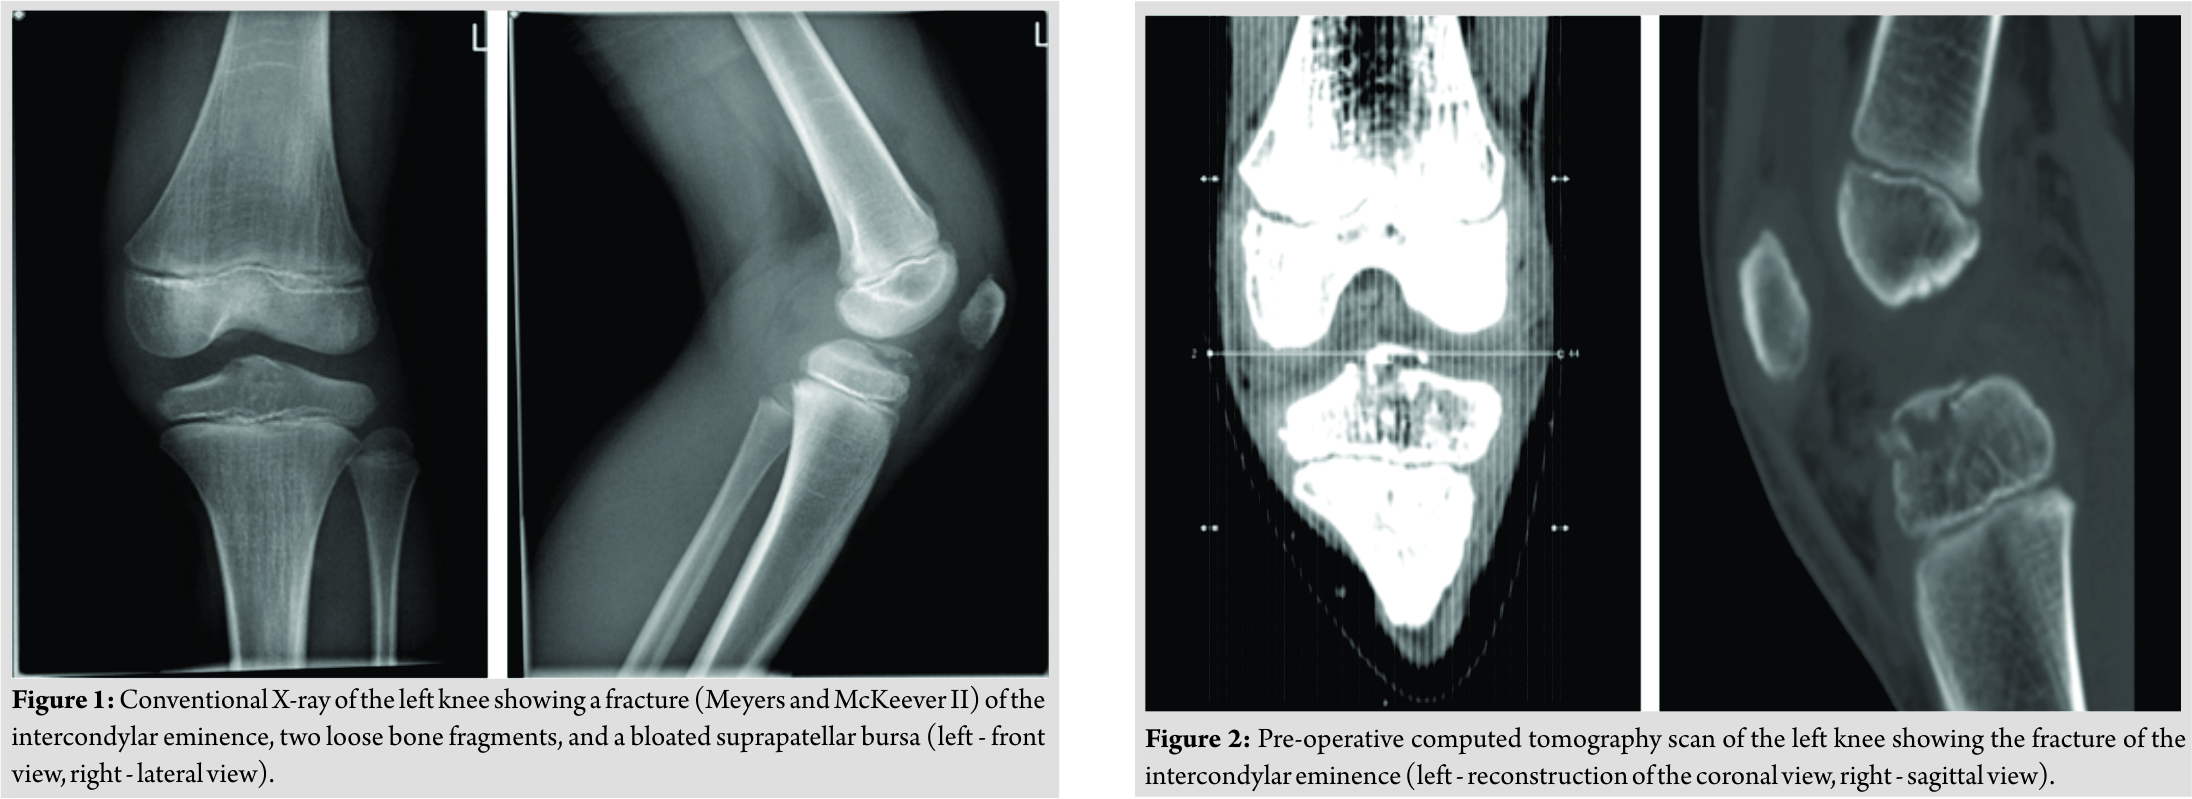

A male Caucasian 8-year-old child presented at the hospital’s emergency department in Belgium. The circumstances of the accident were reported as a fall on the left knee complicated by a contact trauma with another child. At consultation presenting, complaints were a sharp pain in his left knee and difficulties to walk. The pain was scored as 4/10 on the visual analogue scale. In clinical examination, anterior pressure pain, swelling, and a restricted range of motion(flexion up to 100° and extension deficit of 5°) were the main findings. Performing ananterior drawer test and Lachman test, no laxity was documented. On conventional anteroposterior and lateral view of the X-ray, a minimal displaced fracture of the intercondylar eminence, two loose bone fragments, and a bloated suprapatellar bursa indicating hemarthrosis could be evidenced (Fig. 1). A CT scan confirmed a fracture of the intercondylareminence (Fig. 2). The fracture was classified as Meyers and McKeever Type II [4]. The initial treatment provided an adequate pain management with appropriate analgesics and plaster immobilization in 0–5° of flexion. Based on the clinical and radiological findings, a knee arthroscopy was performed 3daysafter injury. The indication for arthroscopic surgery was removal of the intra-articular bony fragments and to evaluate whether the fracture was stable. The fracture of the proximal tibia was visualized through arthroscopy (Fig. 3).